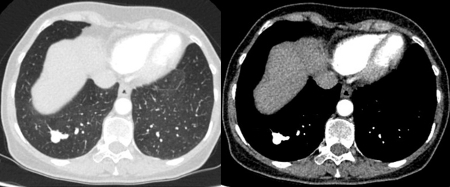

[Figure caption and citation for the preceding image starts]: Tomografia computadorizada (TC) mostrando nódulo sólido apical no lobo superior direito com halo circundante com opacidade em vidro fosco, em paciente com artrite reumatoide soropositiva em uso de metotrexato. Outros nódulos semelhantes foram observados em ambos os pulmões e permanecem estáveis por >2 anos, condizentes com nódulos reumatoides inflamatórios benignosDo acervo de Dr. George Tsaknis, MD, PhD, FRCP (Londres), MRQA, MAcadMEd, PGCert; usado com permissão [Citation ends].